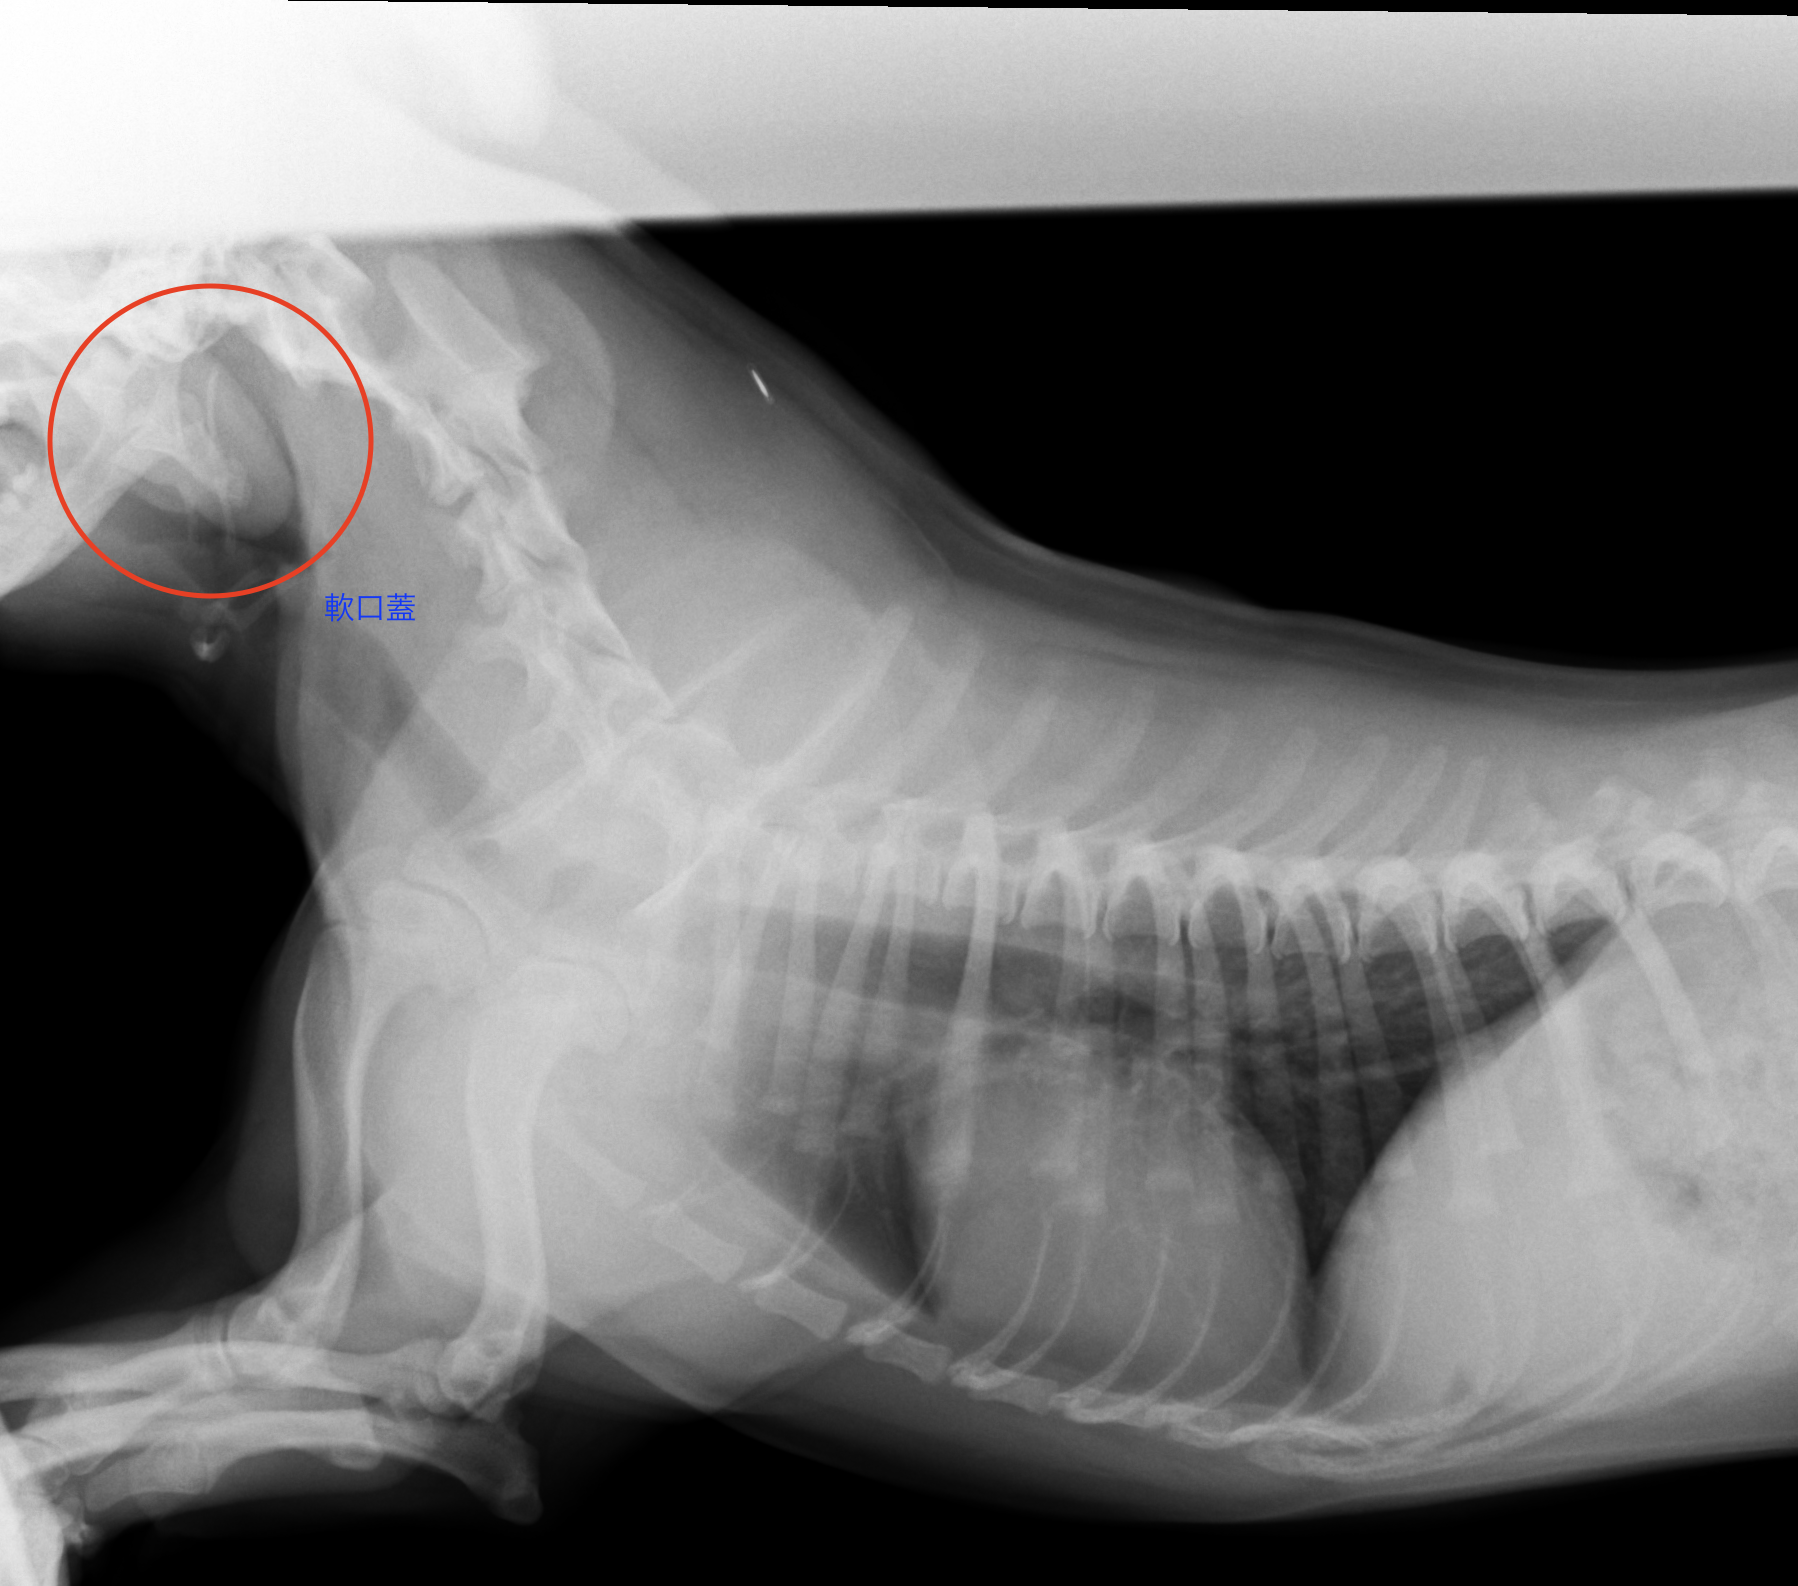

実際のレントゲン画像です

②軟口蓋過長

さらに追加検査としてレントゲンや透視画像を用いてさらなる診断を行います。

もちろん確定診断を行うには内視鏡を用いた検査が正確ではありますが、重度の呼吸器症状が見られる場合などは検査のために麻酔をかけることは危険です。そのため、まずは無麻酔下での検査において診断をしていきます。